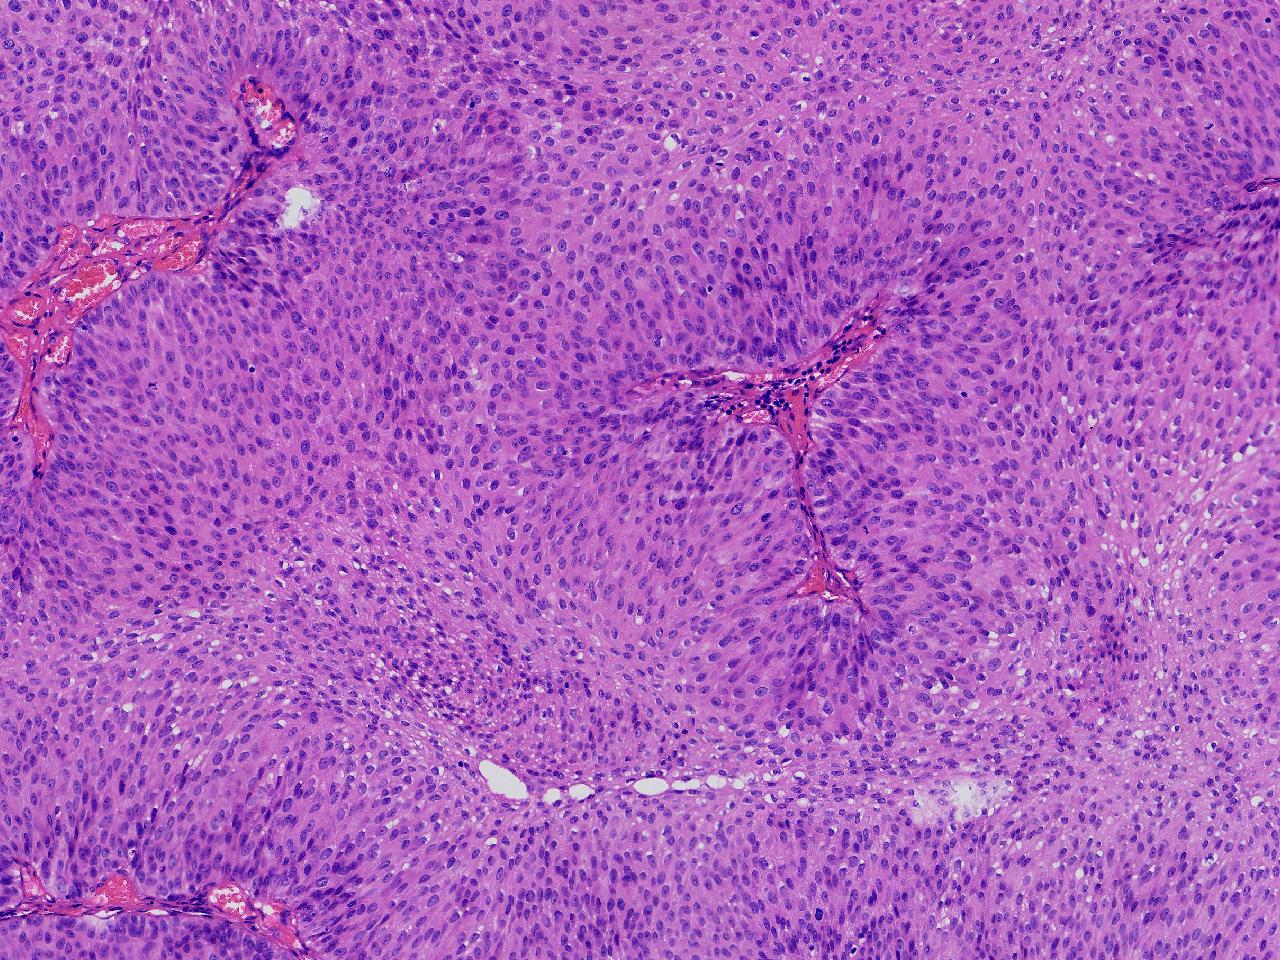

男,79岁,膀胱肿物。

膀胱肿物

灰白色不整形软组织多块,2X1X1厘米。

考虑:乳头状尿路上皮癌

乳头状尿路上皮癌,低级别。

这几张图片上没有看到明确的浸润。